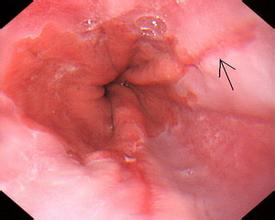

反流性食管炎是怎么回事?

反流性食管炎是胃管反流病常見(jiàn)的一種合并癥。反流性食管炎病人長(zhǎng)期存在胃食管反流,其食管黏膜因長(zhǎng)期、反復(fù)受到反流物的刺激而發(fā)生糜爛,甚至發(fā)生食管狹窄等病變。